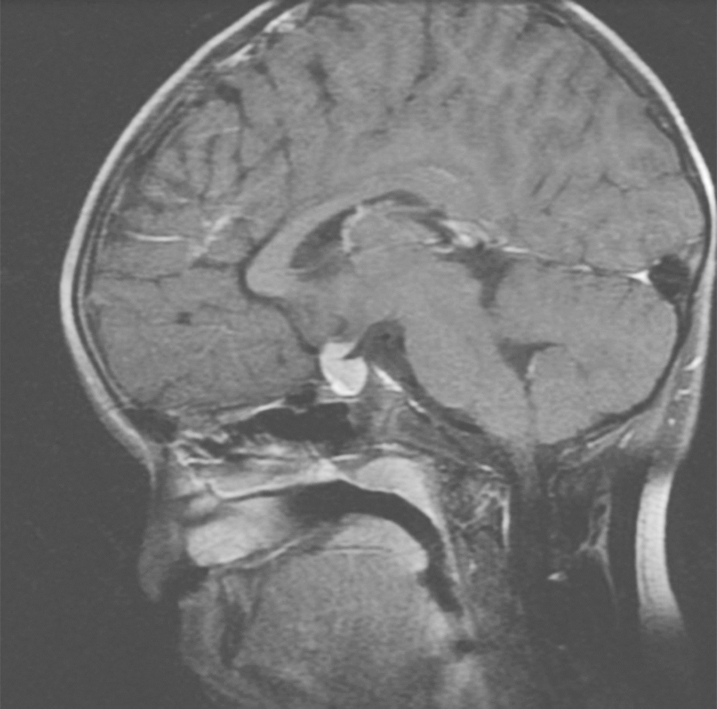

颅内生殖细胞肿瘤的诊断较为困难,结合患者的临床表现,血清和脑脊液的肿瘤标志物、影像学检查,以及手术标本的病理学诊断。对于结合患者临床表现疑诊颅内生殖细胞肿瘤的患者,在完善垂体功能评估和血清及脑脊液中β-hCG、α-甲胎蛋白(AFP)检测的同时,需尽快完善影像学检查。磁共振成像是最优的检查手段,但是CT对了解肿瘤密度、钙化、出血以及脑积水的程度很重要。典型颅内生殖细胞肿瘤T1加权相为底信号或等信号,增强相能被均匀强化(图1)。生殖细胞瘤生长迅速,可以伴有出血坏死表现为核磁影像上的不均一。绒毛膜癌因具有明显的血管化,常表现为肿瘤内出血。畸胎瘤有囊性和实性成分混合,成熟畸胎瘤常表现为可见的脂肪和骨质。大多数生殖细胞肿瘤在影像学上跟松果体和鞍区其他肿瘤难以鉴别,包括松果体室管膜瘤,胶质瘤,郎格汉斯(Langerhans)细胞组织细胞增生症、下丘脑垂体自身免疫炎症以及转移瘤,需要更多的临床线索和诊断证据鉴别诊断。

图1垂体11.2mm×7.8mm×11.2mm,均匀强化,垂体柄横径6.8mm,前后径5.7mm,垂体柄增粗垂体后叶短T1信号未显示,视交叉受压向上移位

引自:内分泌外科学.第1版.ISBN:978-7-117-29197-2.主编:赵玉沛